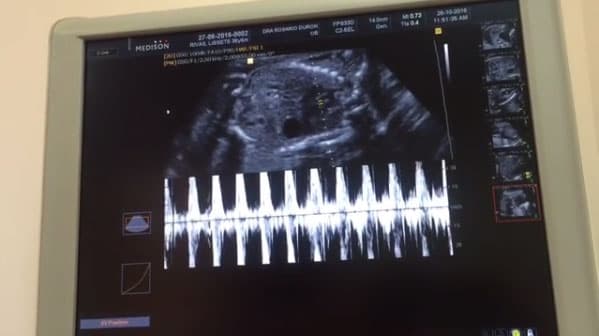

Hace unos meses Julián se convirtió en papá por tercera ocasión. El actor gozó el nacimiento del pequeño Matías quien se ha convertido en una bendición para él y la bella Marjorie de Sousa.